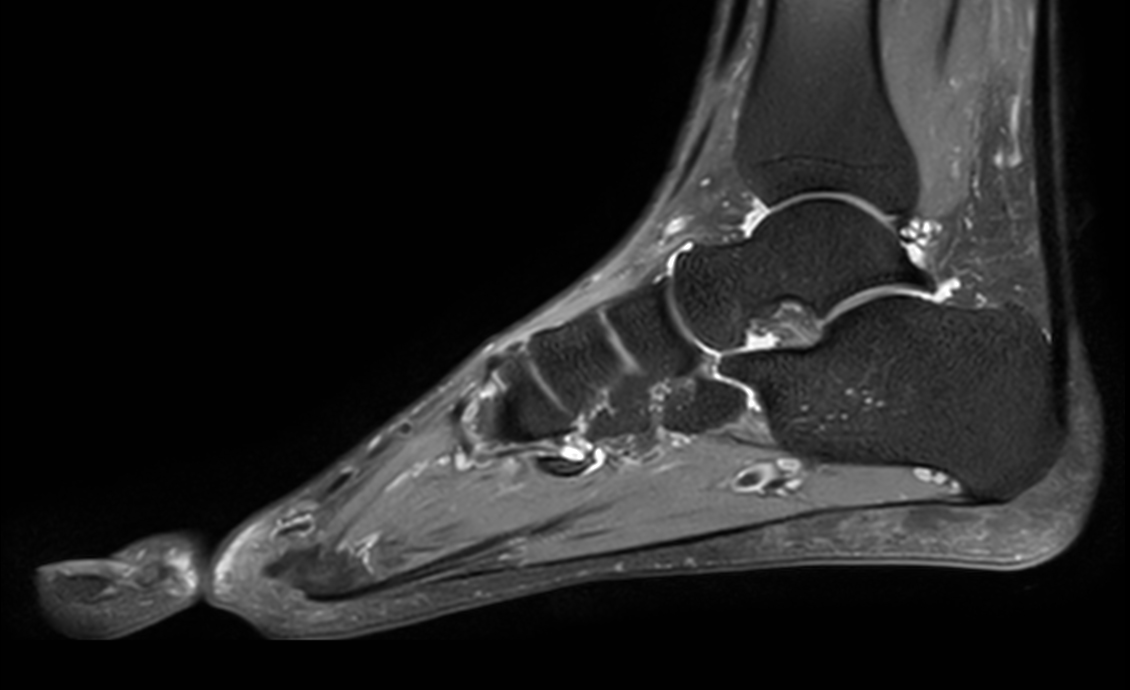

Ankle imaging with the dS 16ch FootAnkle coil

• Clinical Application